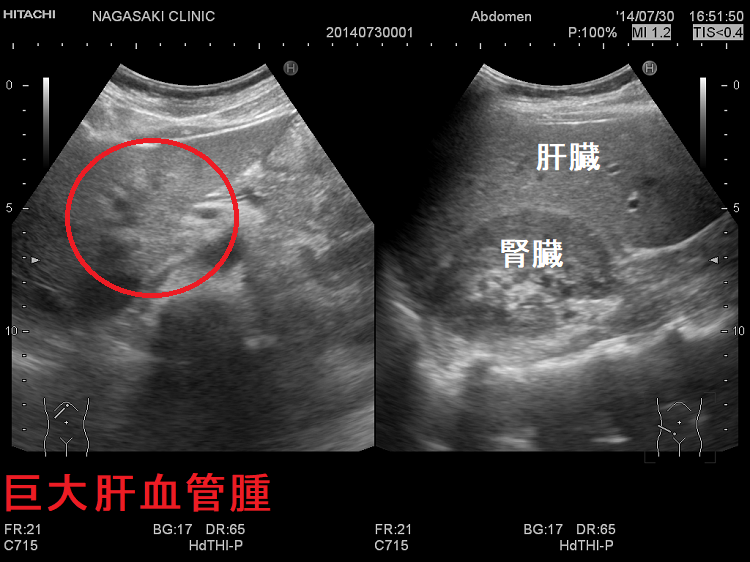

肝血管腫で甲状腺機能低下症

甲状腺乳頭癌の全身転移を検索するためのDWIBS(ドゥイブス) で、偶然見つかった肝血管腫